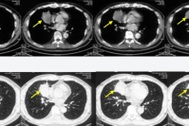

Diễn viên từng đoạt giải Grammy Kathy Griffin bị ung thư phổi

Nữ diễn viên 61 tuổi Kathy Griffin vừa thông báo tình trạng bệnh của mình trên trang cá nhân.